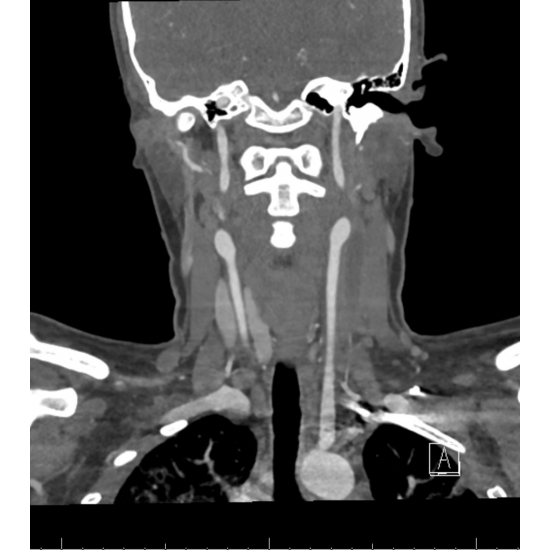

Two days later, she underwent a CT Angiogram of the neck: With mild to moderate left submandibular adenopathy. Occlusive thrombus within left internal jugular vein from C3 level down to the thoracic inlet, involving a 9 cm long segment, compared to the reported 3.1 cm long segment on the duplex sonography. Case Photo #6 and Case Photo #7